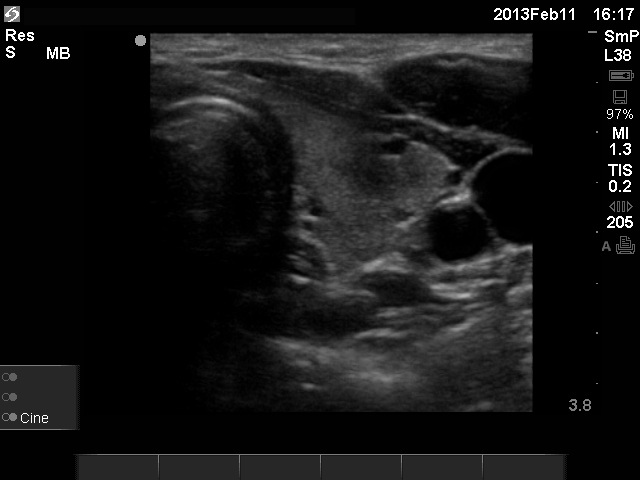

Initial examination (first row of images):

Clinical presentation: A 29-year-old woman requested a second opinion. She was in the 11th week of her pregnancy. She had mild neck discomfort for 2 months. A suspicious nodule was found in the left lobe on the evaluation. Aspiration cytology was repeatedly non-diagnostic. She was told that she had thyroid carcinoma with great probability. Her endocrinologist recommended to abort the child and then to undergo thyroidectomy.

Palpation: The left thyroid was hard on palpation, but not painful.

Ultrasonography: The right thyroid was echonormal and contained several small, insignificant lesions. There was a hypoechogenic lesion with blurred borders in the central and in the ventro-medial part of the left thyroid with increased intranodular blood flow.

Aspiration cytology resulted in thyroiditis, not otherwise specified.

Laboratory tests: subclinical hyperthyroidism. Serum-calcitonin, anti-TPO, anti-hTg, TSAb resulted in normal values.

Combined clinical-sonographic-cytological diagnosis: subacute, de Quervain's thyroiditis.